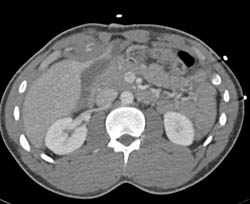

Bleed in and Near Liver S/p Stab Wound